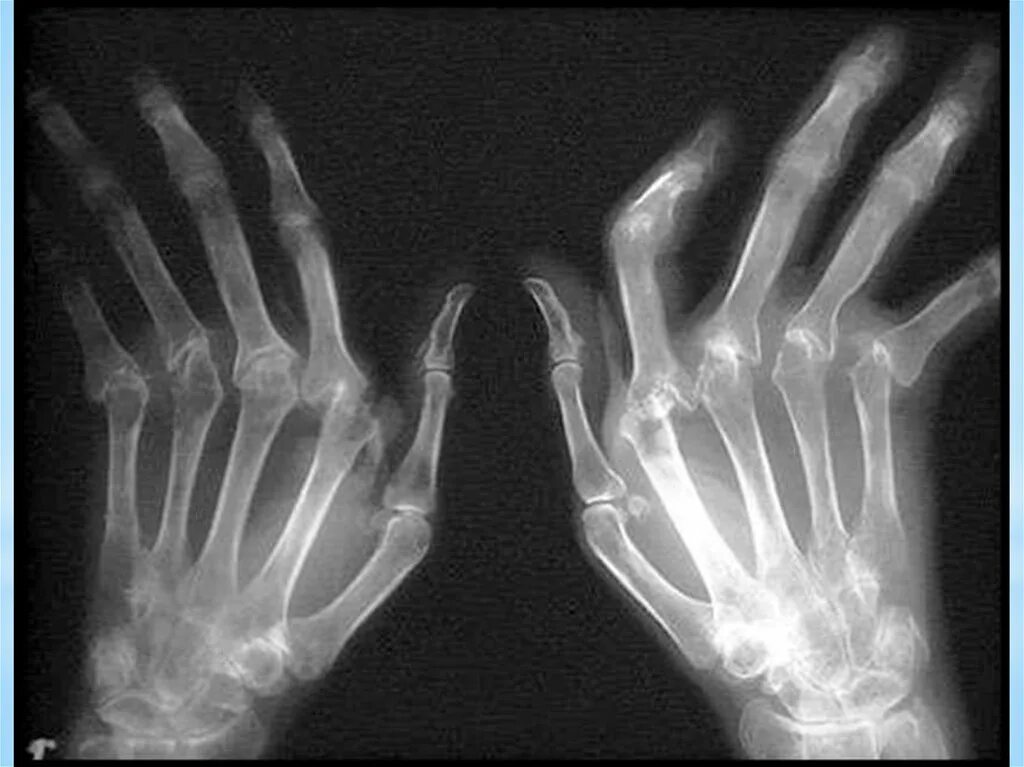

Ревматоидный артрит деформация кисти. ревматоидный полиартрит рентген. ревматоидный артрит запястного сустава. полиартрит рентген кистей.

Типы деформации при ревматоидном артрите. деформация кистей при ревматоидном артрите. ревматоидный артрит девиации. латеральная девиация суставов кистей.

Ревматоидный артрит кисти рентген. ревматоидный артрит деформация кисти. полиартрит рентген кистей. ульнарная девиация кисти рентген.

Ульнарная девиация кисти ревматоидный артрит. деформация кистей при ревматоидном артрите. деформация кисти по типу лорнетки.